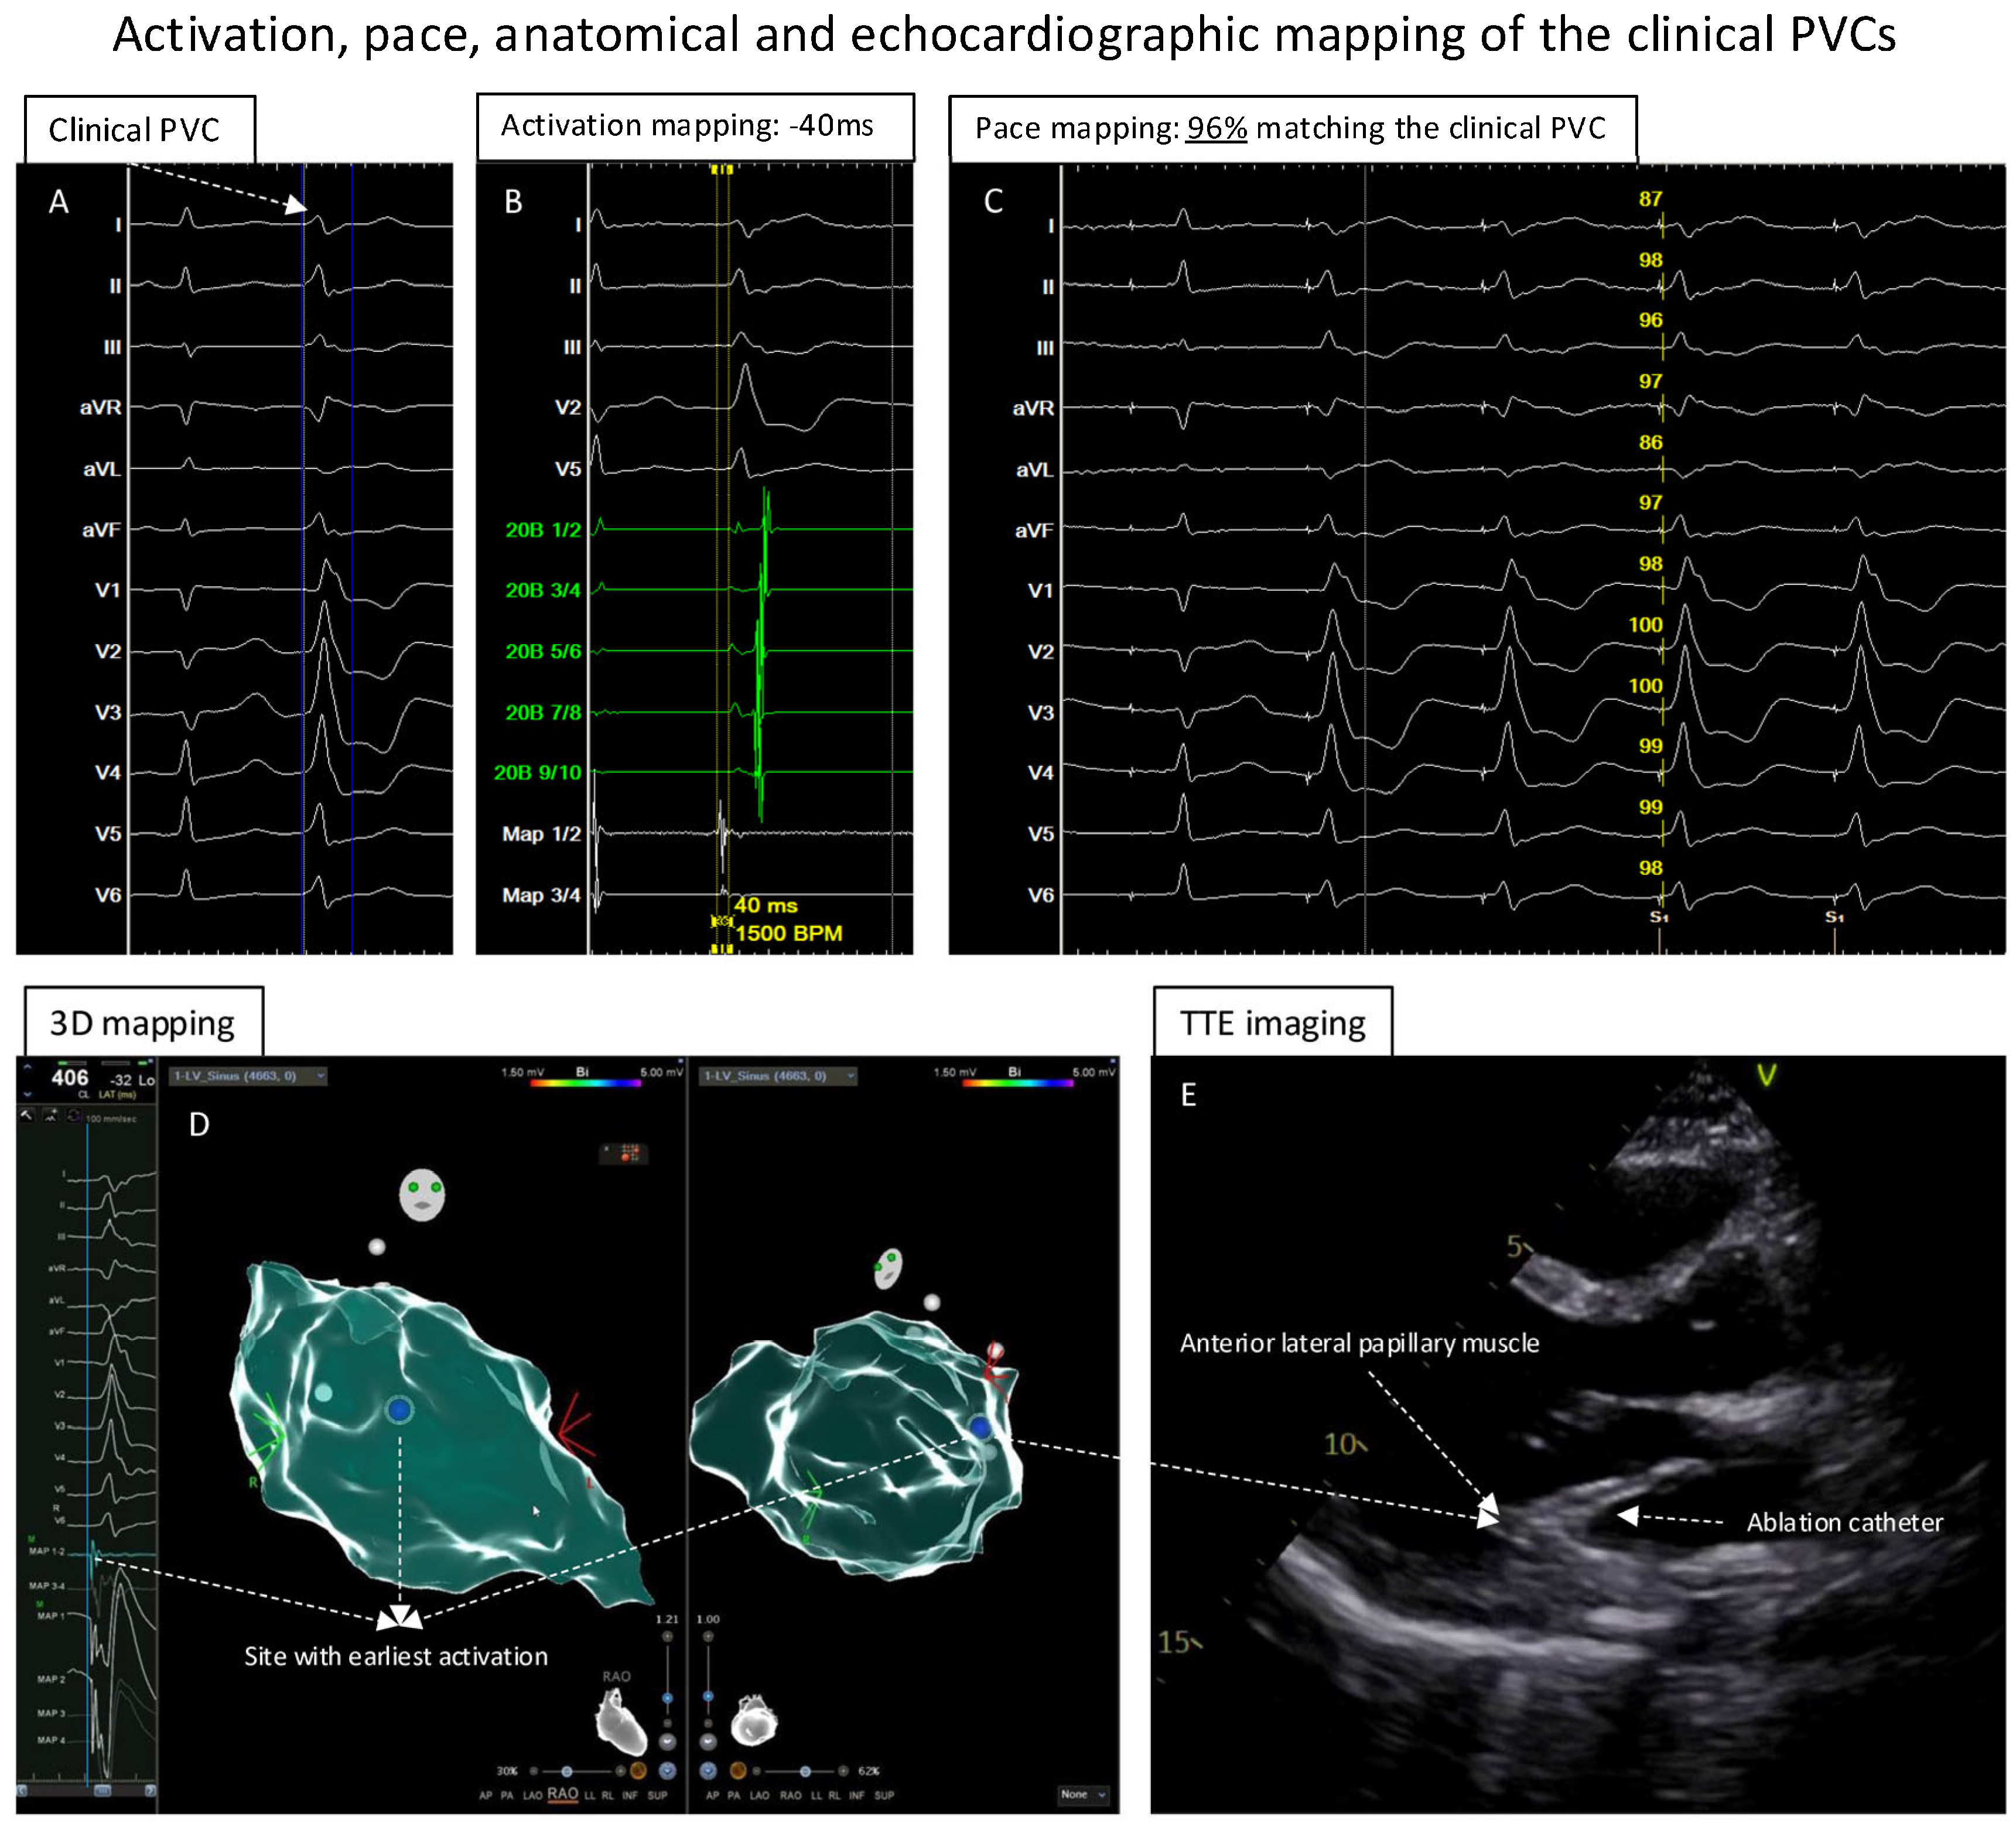

Mapping and Ablation of the PVCs